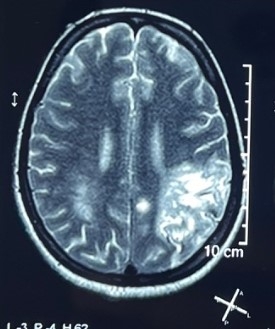

CEMRI BRAIN showed subacute infarct with hemorrhagic transformation in left parietal, temporal and occipital lobe, subacute infarct in left frontal lobe, foci of FFE in blooming in anterior limb of right and posterior limb of left internal capsule.CT angiography revealed diffuse mural thickening in the aortic arch,ascending and descending aorta, marked narrowing in the brachiocephalic artery and both common carotids, with saccular aneurysms, attenuation of intracranial ICA, ACA, and MCA, particularly on the right side.